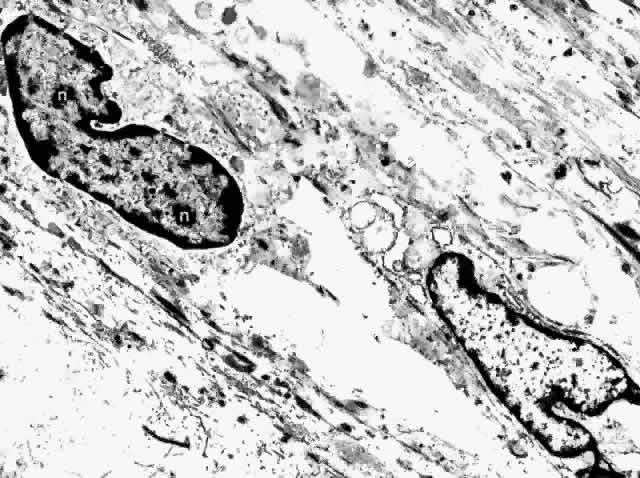

The fibrocyte is the most common nonpigmented cell found in the choroid (Fig. 31). Its long, spindle-shaped body and processes intermingle with the melanocytes in the outer choroid, forming syncytia. They are present throughout the vessel layers and only rarely are seen in the subcapillary zone of collagen. The cytoplasm of the fibrocyte contains mitochondria, Golgi apparatus, centrioles, free ribosomes, and rough endoplasmic reticulum.17,22

Fig. 31. Choroidal fibrocytes display nuclei with several nucleoli (n). Extracellular collagen is apparent. (× 9000)